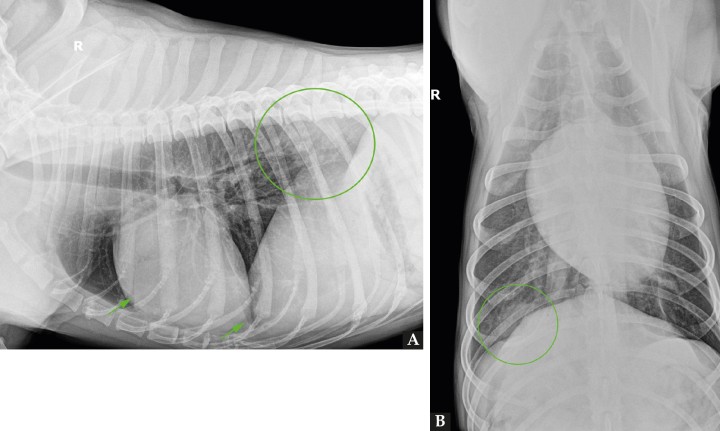

En la proyección lateral derecha se evidencia un patrón intersticial no estructurado en el aspecto dorsal de los lóbulos pulmonares caudodorsales que impide la correcta visualización del pilar diafragmático derecho a dicho nivel; en este caso, la proyección presenta una rotación significativa la cual posiblemente haya permitido visualizar la lesión radiológica con mayor claridad (Fig. 2A). Asimismo, en la proyección ventrodorsal se localiza en la zona de proyección del lóbulo pulmonar caudal derecho un foco de patrón intersticial no estructurado junto a una lesión de tipo nodular y bordes mal definidos, en la zona de proyección de la décima costilla (Fig. 2B). Se observa, además, la presencia de fisuras pleurales, indicativas de efusión pleural leve bilateral. El resto de las estructuras evaluables no muestran alteraciones reseñables.

<p>Mismas radiografías que Figura 1. (<strong>A</strong>) Radiografía de tórax en proyección latero-lateral derecha; resaltado se observa un patrón intersticial no estructurado a nivel caudodorsal (círculo) que impide la correcta visualización del pilar diafragmático derecho. Además, se evidencia la presencia de fisuras pleurales (flechas). (<strong>B</strong>): Radiografía de tórax en proyección ventrodorsal; resaltado se evidencia un patrón estructurado de tipo nodular en la zona de proyección de la décima costilla (círculo).</p>

Mismas radiografías que Figura 1. (A) Radiografía de tórax en proyección latero-lateral derecha; resaltado se observa un patrón intersticial no estructurado a nivel caudodorsal (círculo) que impide la correcta visualización del pilar diafragmático derecho. Además, se evidencia la presencia de fisuras pleurales (flechas). (B): Radiografía de tórax en proyección ventrodorsal; resaltado se evidencia un patrón estructurado de tipo nodular en la zona de proyección de la décima costilla (círculo).